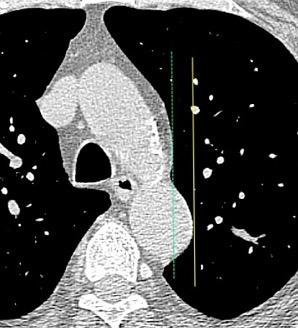

32 años .Preeclampsia a los 19. Hipertensión no controlada. Masa paravertebral sólida que se realza intensamente con afectación ósea.

Yue Y t al. Asymptomatic left posterior mediastinal functional Paraganglioma. A case report. Medicine . 2019